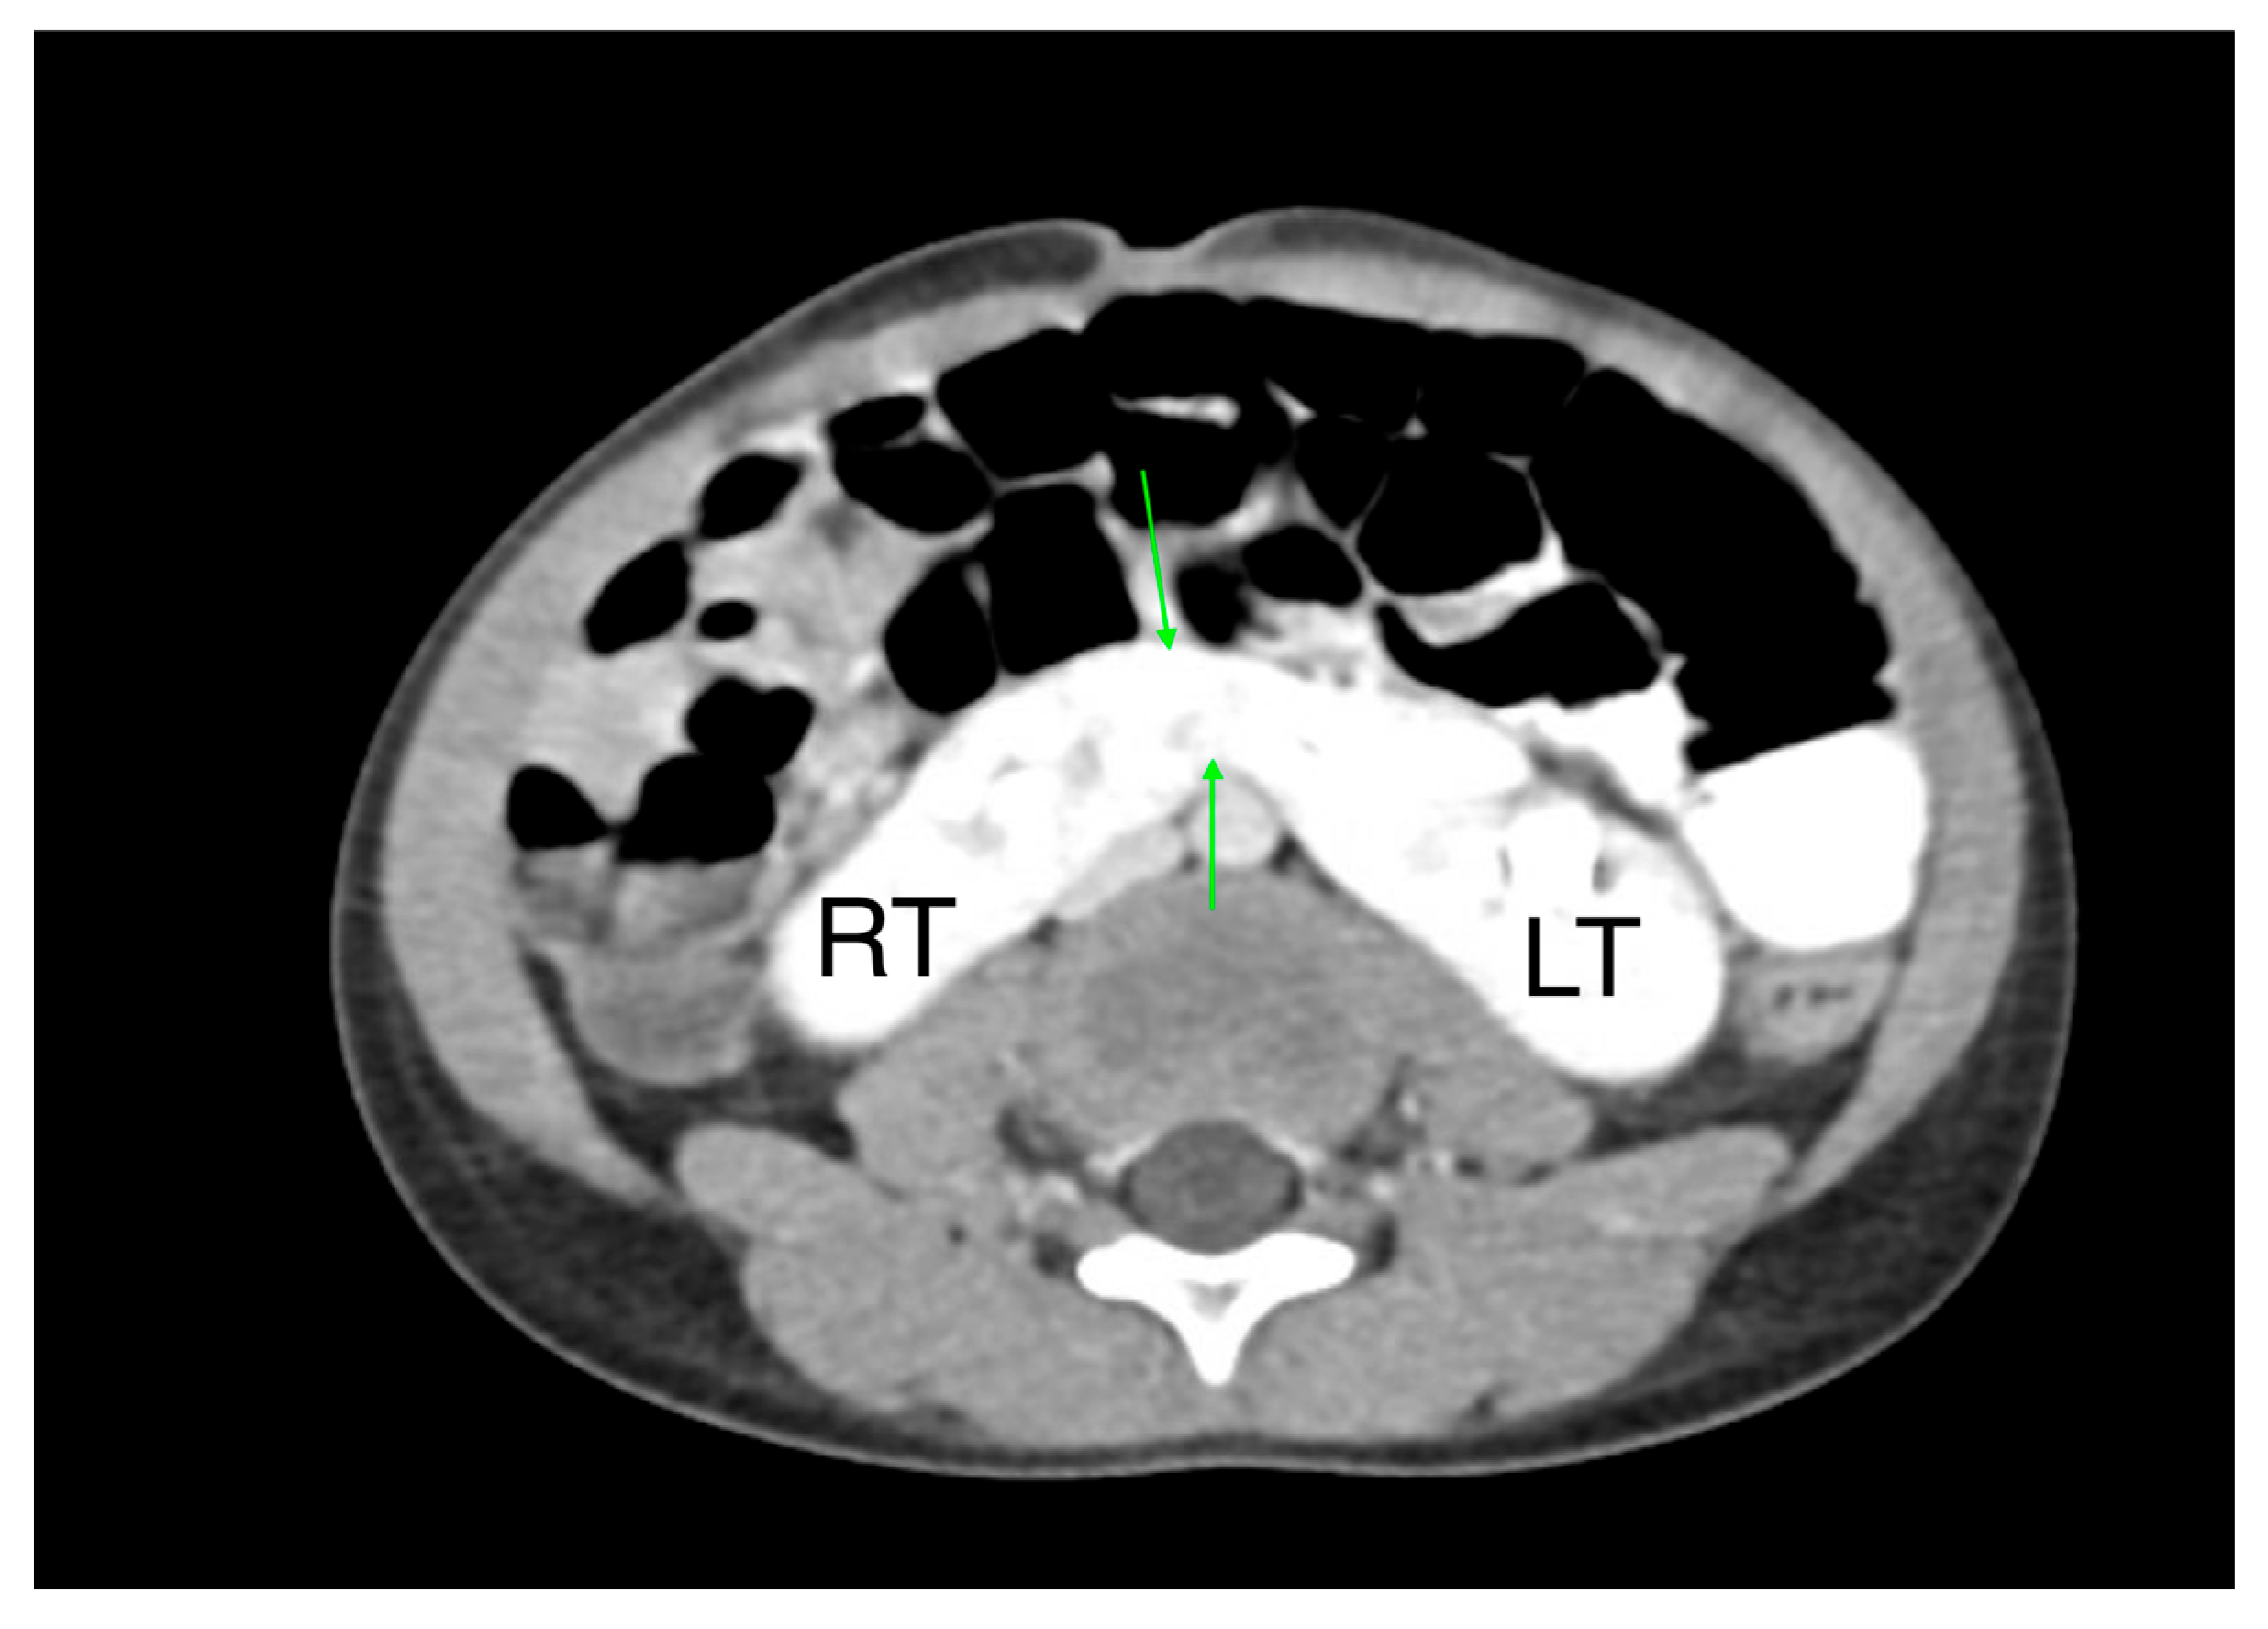

15. Horseshoe and Ectopic Kidneys

- A horseshoe kidney is the most common renal fusion anomaly, occurring in about 1 in 400 live births. In this condition, both kidneys are fused at their lower poles, forming a “horseshoe” shape (Figure 14)

- Renal ectopia occurs in approximately 1 in 900 births and is typically unilateral. In about 40% of cases, the ectopic kidney is located in the pelvis. Crossed ectopia occurs when one kidney crosses the midline and fuses with the other, often resulting in a “crossed-fused” appearance.